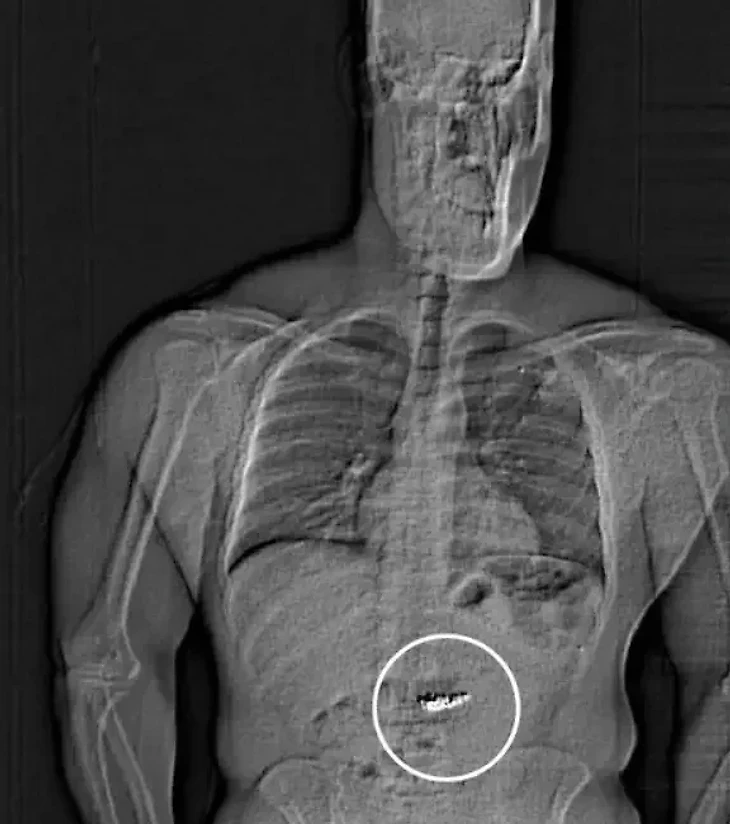

По данным местного издания, вор выбежал из магазина с двумя наборами сережек. Полиция задержала Гилдера на межштатной автомагистрали и предъявила обвинение в сопротивлении аресту, однако не смогла найти у него украденные серьги и предъявить обвинение в краже. Позже в тюрьме задержанный признался, что серьги находятся у него в желудке, что потом подтвердила МРТ.